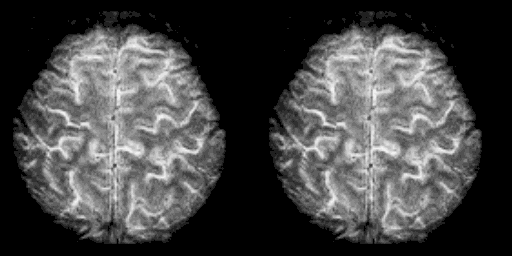

고해상도 fMRI 뇌 스캔 — TRIBE v2가 예측하는 70,000개 복셀 수준의 뇌 활성화는 이처럼 전체 뇌 피질을 상세히 매핑한 결과물

▲ 고해상도 fMRI 뇌 스캔 — TRIBE v2는 이와 같은 70,000개 이상의 복셀에 대해 자극별 뇌 활성화 패턴을 예측합니다. 기존 모델(~1,000 복셀)과의 해상도 차이가 이 그림에서 직관적으로 와닿습니다 | Source: Wikimedia Commons

TRIBE v1(및 이전 유사 모델)은 약 1,000개의 복셀(뇌의 3D 픽셀)을 예측했습니다. TRIBE v2는 약 70,000개의 복셀을 예측합니다. 전체 뇌 피질 표면에 대한 세밀한 활성화 지도를 그릴 수 있게 된 것입니다. 1,000픽셀 이미지 vs. 70,000픽셀 이미지의 차이라고 생각하면 됩니다.